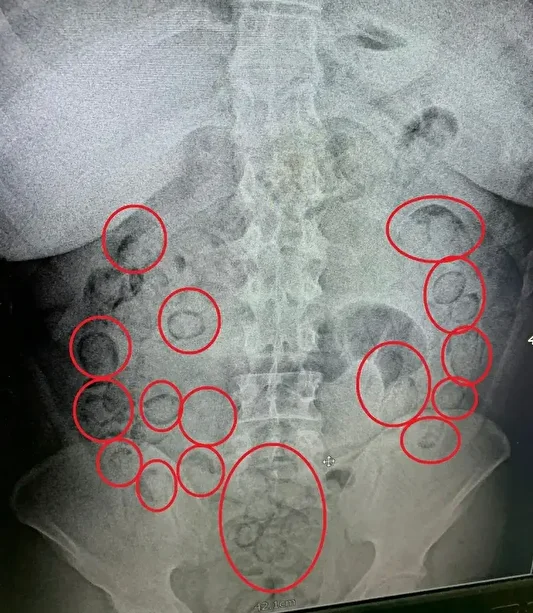

Uyuşturucuları midesine yutarak muhafaza ettiği düşünülen A.M., Aksaray Eğitim ve Araştırma Hastanesi’ne götürülerek iç beden muayenesinden geçirildi.

Çekilen tomografide, şahsın midesinde vücut dışı parçaların olduğu tespit edildi. Doktor kontrolünde ilaç içirilen tacirin, bir süre sonra polis nezaretinde yaptığı büyük tuvaletinde, prezervatife sarılmış 101 küçük paket çıktı.

Paketlerin içerisinden toplam 433 gram metamfetamin maddesi ele geçirildi. Uyuşturucu maddelere el konulurken, emniyetteki işlemlerinin ardından adli makamlara sevk edilen İran uyruklu uyuşturucu taciri tutuklanarak cezaevine gönderildi.